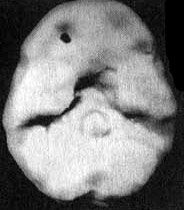

Отсутствие активности в левой височной доле у Эндрю

Трехмерное изображение нижней поверхности мозга

Нормальный мозг

Мозг Эндрю - левой височной доли не видно

Вместе с Эндрю я отправился в отделение сканирования и, пока проводилось исследование, держал его за руку. Эндрю усадили в кресло, в вену ввели иглу, а через нее - малую дозу радиоизотопов. В это время Эндрю играл на ноутбуке в игру на концентрацию внимания. Через несколько минут иглу вынули, и он пошел в соседний кабинет, где делались снимки. Там его уложили на спину на специальный стол. В течение пятнадцати минут камера, медленно двигавшаяся по окружности вокруг головы Эндрю, производила съемку его мозга. Когда изображение было выведено на экран монитора, я подумал, что в ходе исследования была допущена какая-то ошибка. У Эндрю отсутствовала левая височная доля. Просмотрев все снимки, я убедился, что качество сканирования - хорошее. У него на самом деле не было левой височной доли. Что у него было? Киста? Опухоль? Инсульт? Рассматривая эти снимки на мониторе, я испытывал за него сильный страх. В то же время я чувствовал облегчение от того, что мы установили причину его агрессивности. В своих исследованиях и я, и мои коллеги установили связь между нарушениями в левой височной доле и агрессивностью. На следующий день на магнитно-резонансной томографии мы обнаружили у Эндрю на том месте, где обычно находится левая височная доля, кисту (мешок, заполненный жидкостью), размером с мячик для гольфа. Я знал, что эту кисту надо убрать. Однако поиск специалиста, который серьезно отнесся бы к нашим выводам, оказался трудным.